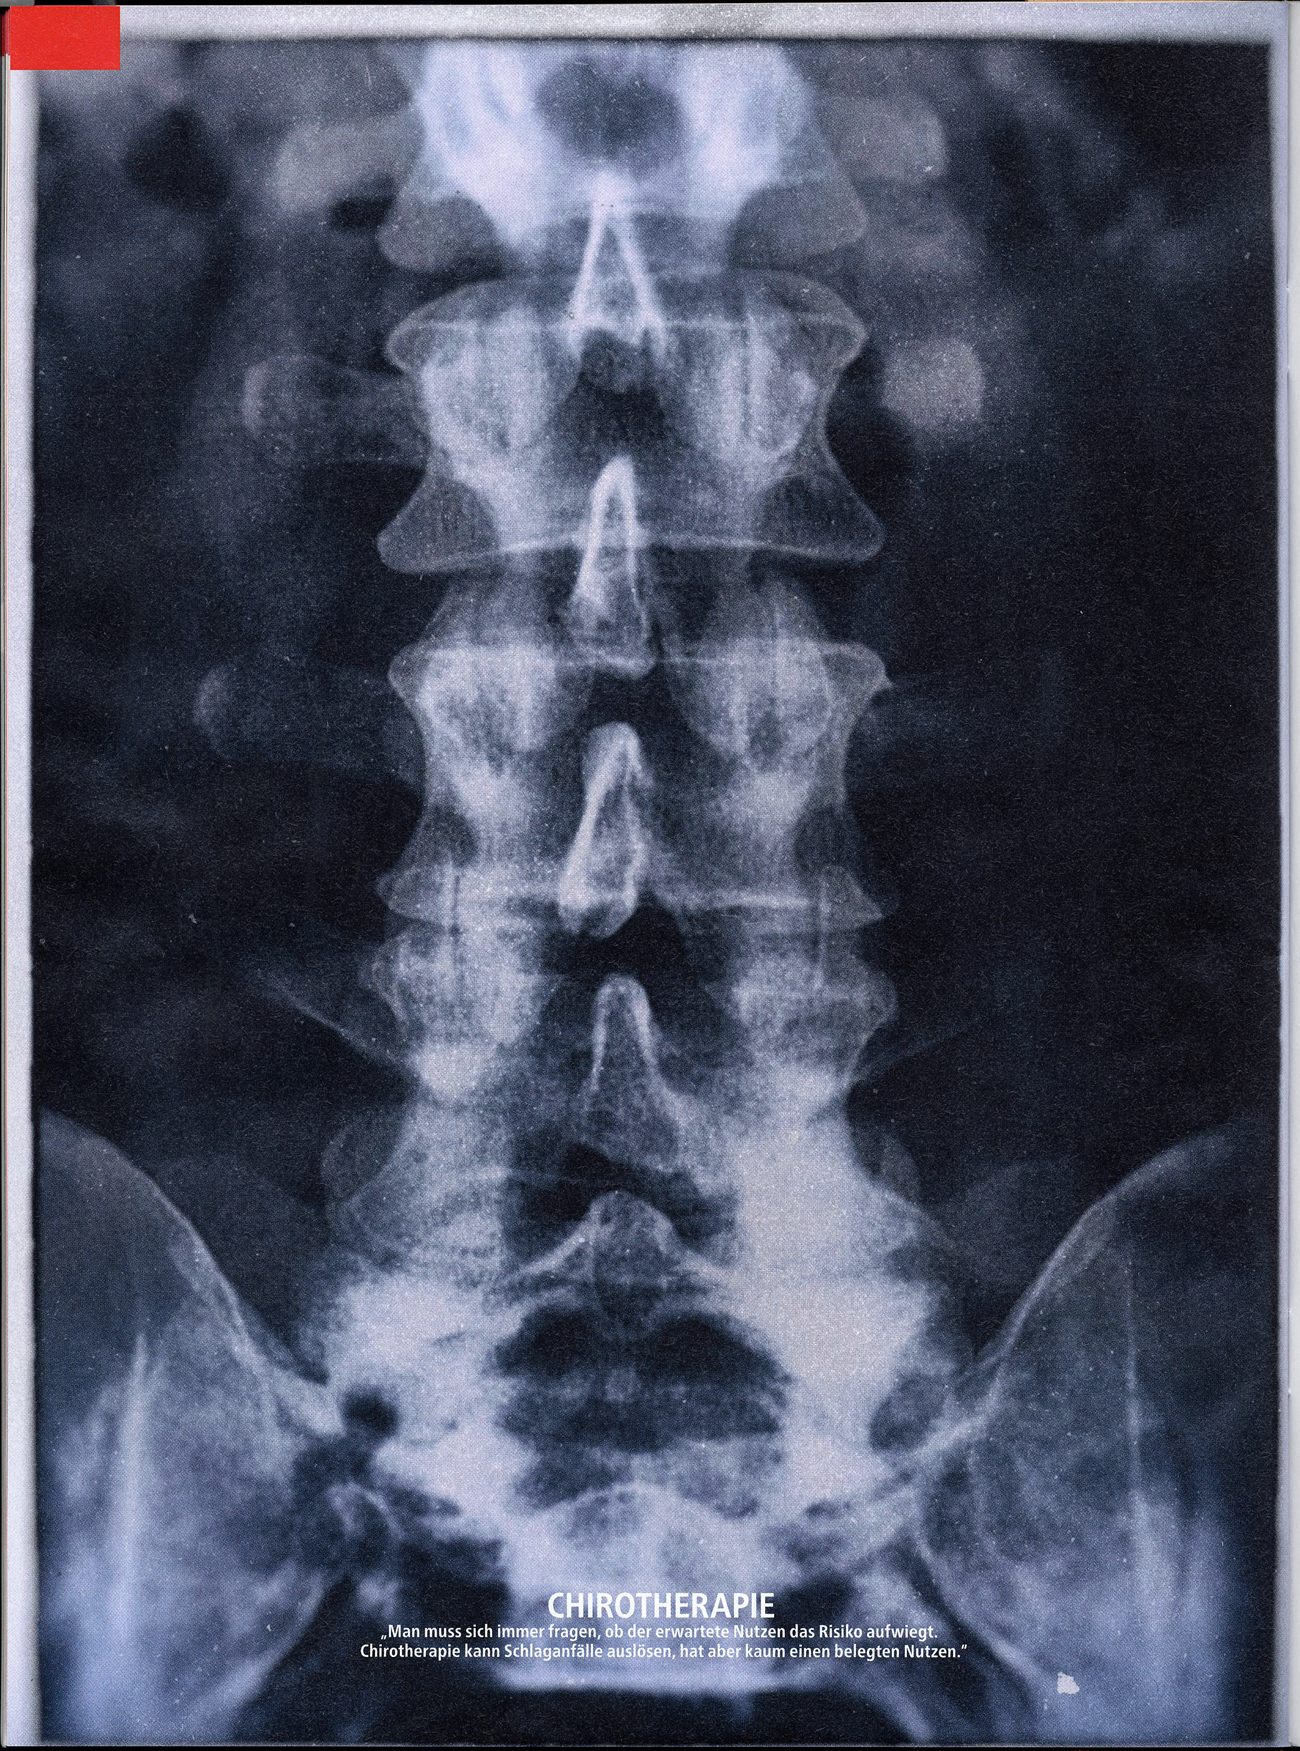

Seite 76